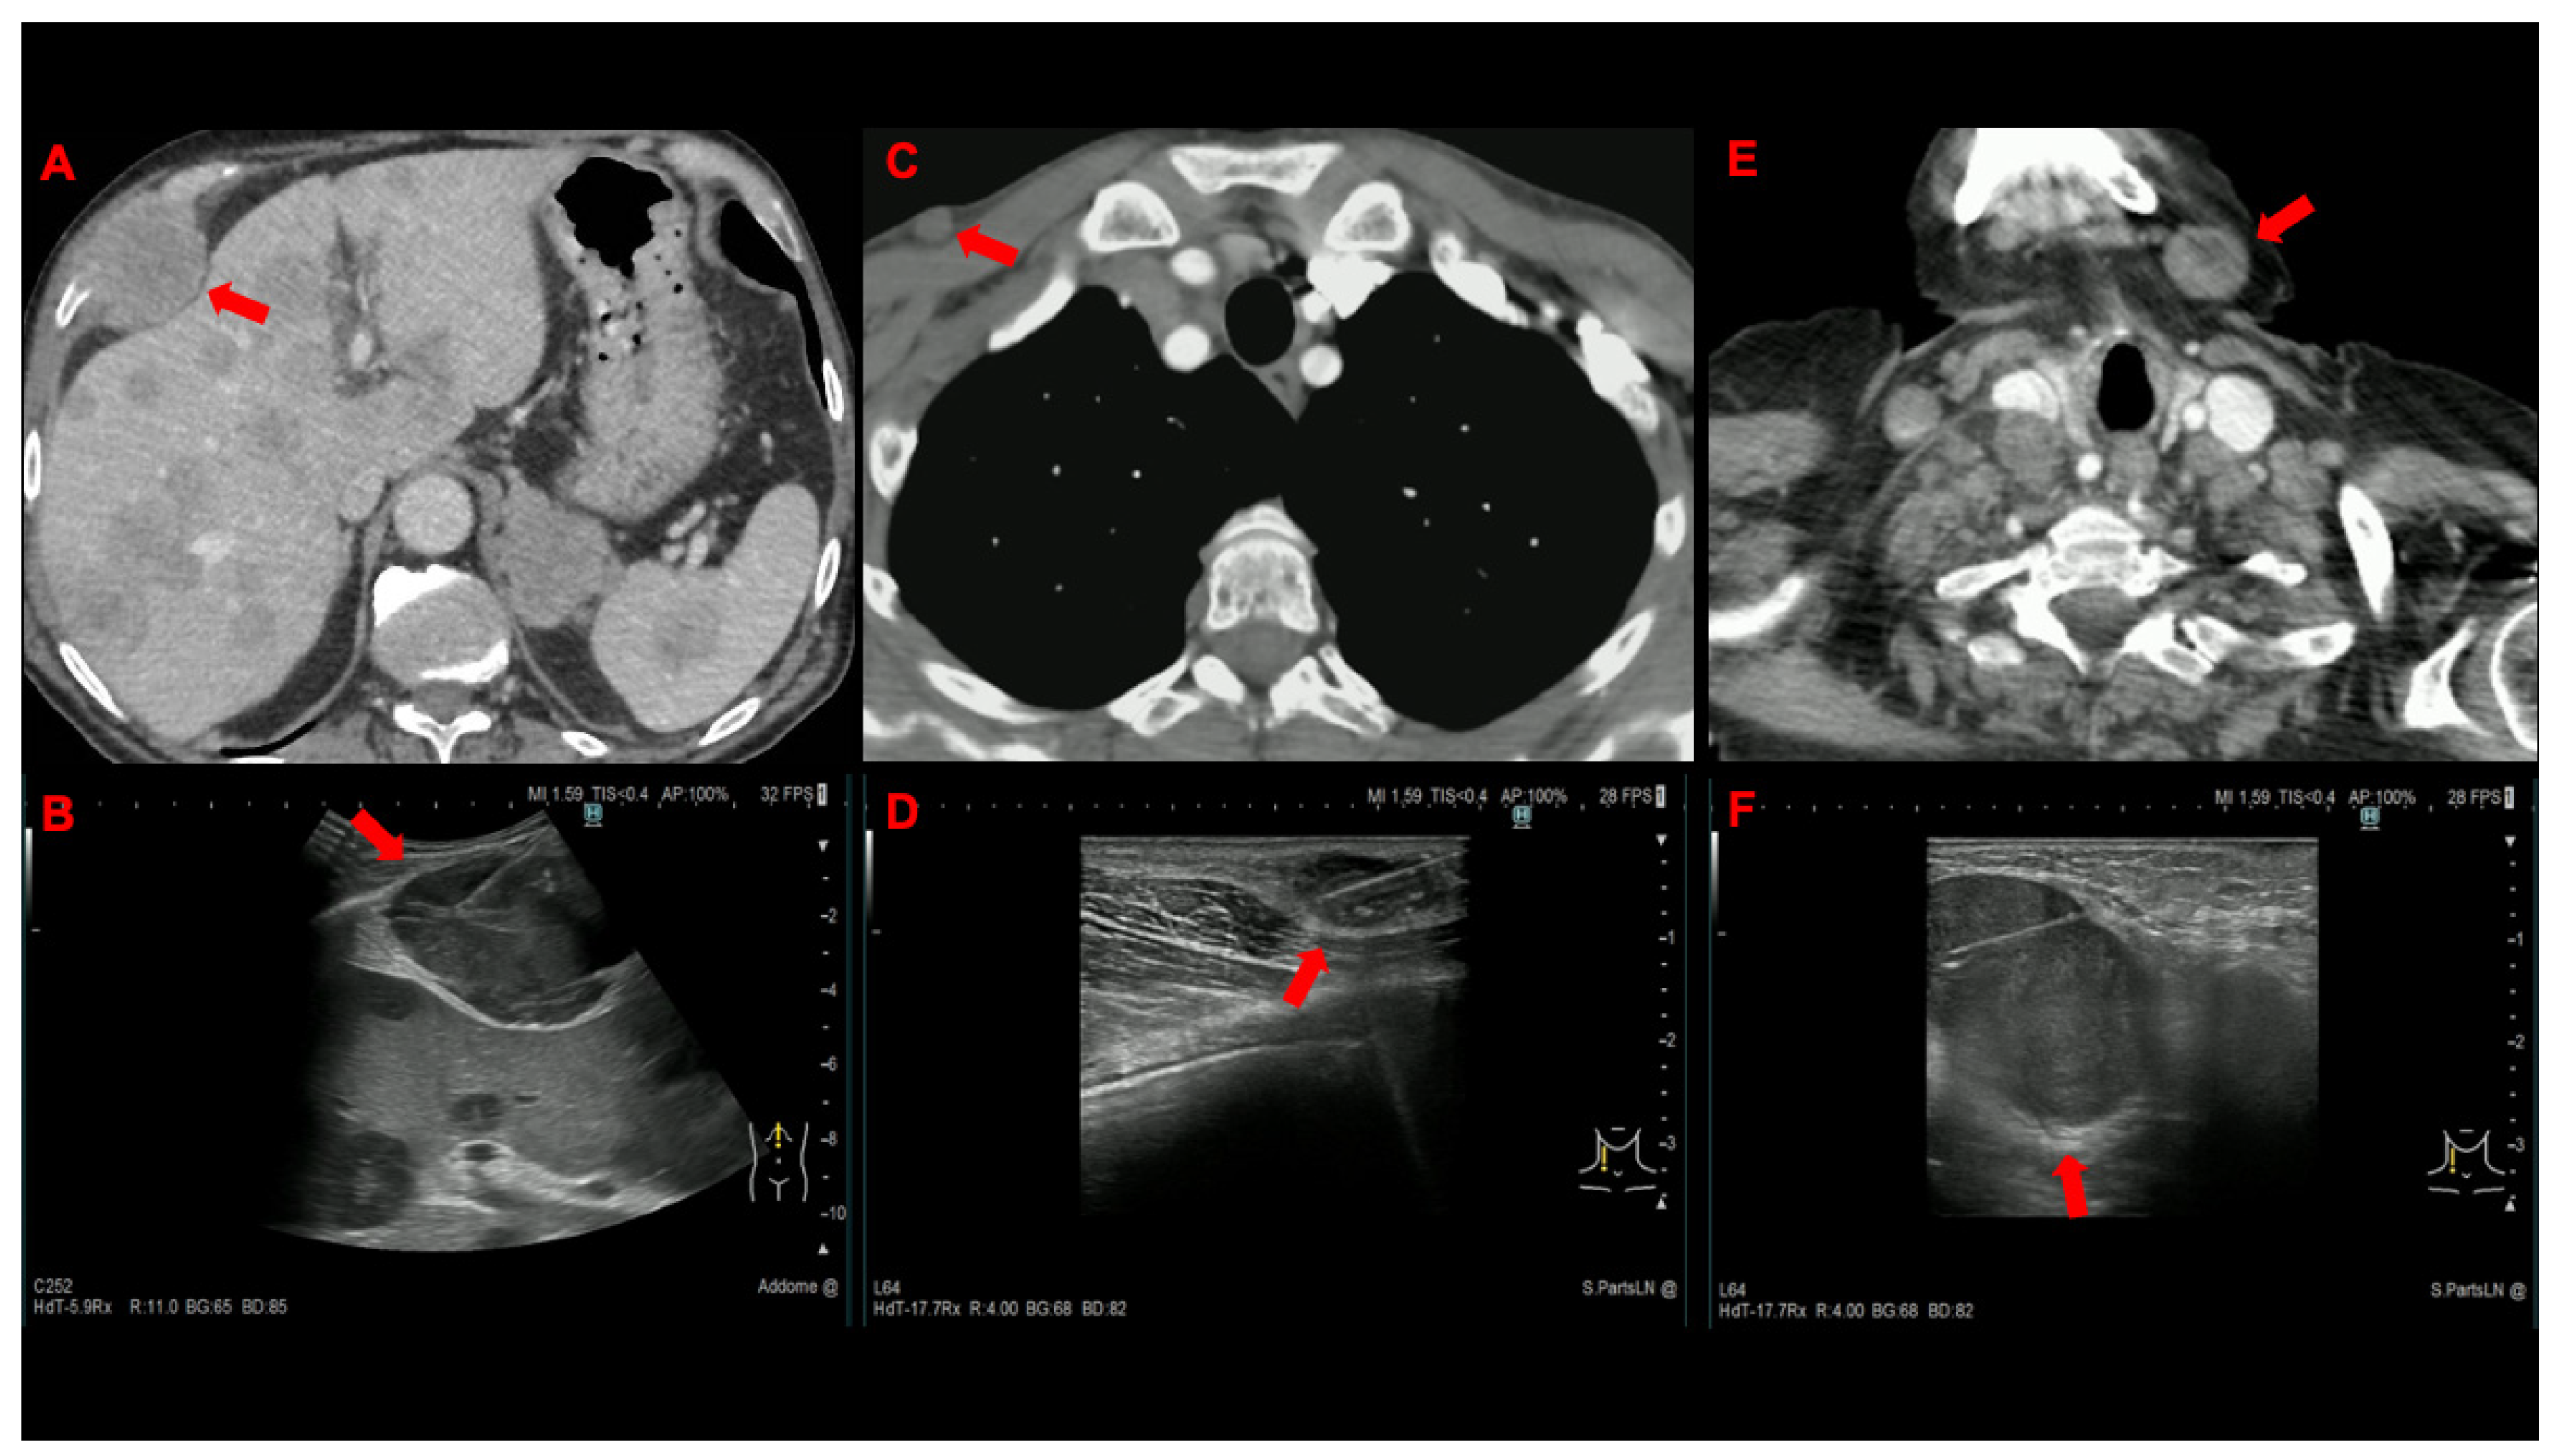

| Metastatic site, n. (%) | ||

| Lymph node | 54 (75) | 49 (68) |

| Supraclavicular | 44 | 40 |

| Cervical | 8 | 7 |

| Axillary | 2 | 1 |

| Mammary | 0 | 1 |

| Bone | 7 (9.7) | 11 (15.3) |

| Subcutaneous tissue | 6 (8.3) | 6 (8.3) |

| Thoracic wall | 3 (4.2) | 3 (4.2) |

| Muscle | 2 (2.8) | 1 (1.4) |

| Pleura | 0 (0) | 2 (2.8) |